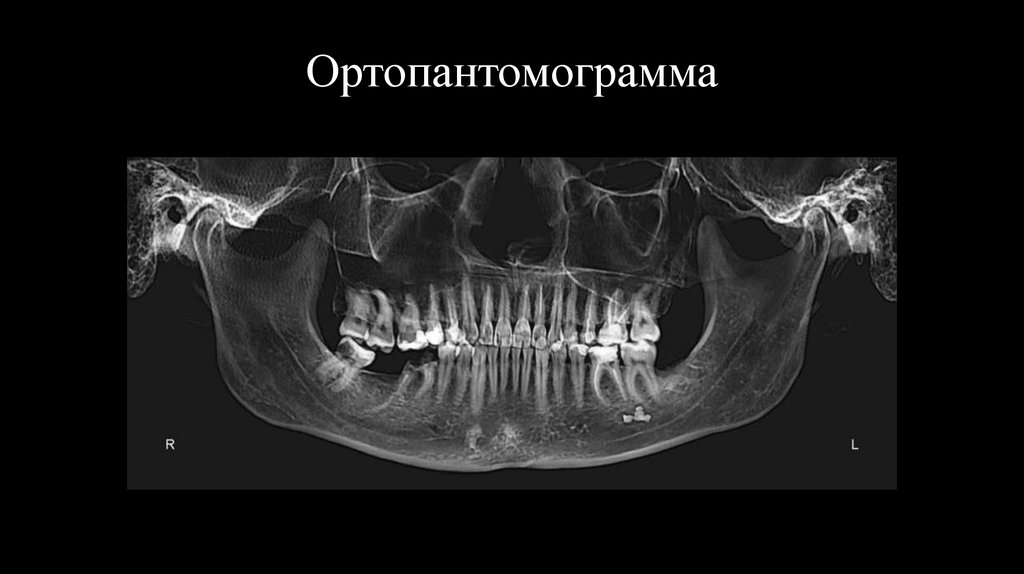

11. Ортопантомограмма

Зуб 3.7 отсутствует. Разрушение коронковой части зуба 3.6.

Отсутствие зуба 3.7. корни зуба 3.6.